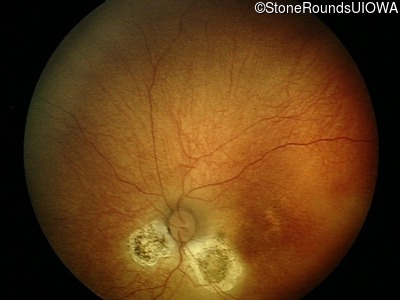

Fundus Photography - Right - 20/60 -2 sc

Exemplar

Fundus Photography - Left - 20/60 -2 sc